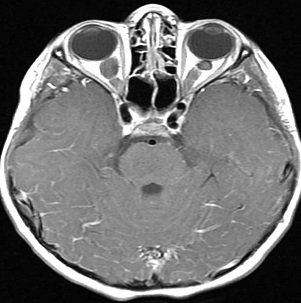

4、CT掃描:可為單側(cè)發(fā)病,也可為雙側(cè)發(fā)病,后者常伴發(fā)神經(jīng)纖維瘤病,并且兩側(cè)發(fā)病順序可不一致,應(yīng)引起重視。視神經(jīng)增粗扭曲為視神經(jīng)膠質(zhì)瘤較常見的表現(xiàn)。由于腫瘤壓迫,常使其前端的正常蛛網(wǎng)膜下腔擴(kuò)大。視神經(jīng)膠質(zhì)瘤眶內(nèi)部分為視神經(jīng)梭形或橢圓性腫大,也可呈管狀增粗,邊界清楚,密度均勻,腫瘤內(nèi)常見低密度的囊變區(qū)。約3%的腫瘤內(nèi)可見鈣化。

5、MRI檢查:表現(xiàn)為視神經(jīng)呈梭形、冠狀或橢圓形增粗,多數(shù)為中心性,少數(shù)為偏心形。與正常眼外肌比較,視神經(jīng)膠質(zhì)瘤在T1WI呈低信號(hào),T2WI呈高信號(hào),增強(qiáng)后中度強(qiáng)化。部分腫瘤壓迫使其前部正常的蛛網(wǎng)膜下腔擴(kuò)大,表現(xiàn)為與腦脊液信號(hào)相似的長T1、長T2信號(hào);由于少數(shù)腫瘤周圍蛛網(wǎng)膜等結(jié)構(gòu)反應(yīng)性增生而形成假性包膜,表現(xiàn)為長T1、長T2 。